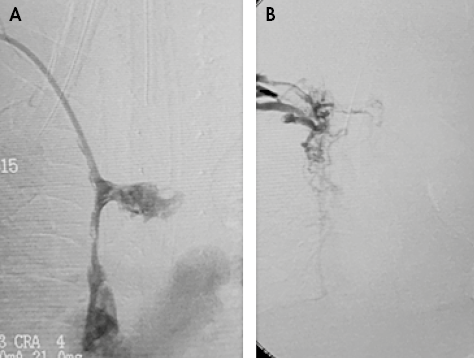

Due to the persistent increase in the diameter of the neck after catheter removal, a Doppler ultrasound of the neck and large vessels was requested, which revealed thrombosis of the superior vena cava without involvement of the jugular and subclavian vein junction in the right atrium. For this reason, it was decided to initiate anticoagulation with low-molecular-weight heparin considering the high risk of paradoxical pulmonary thromboembolism caused by the persistence of the patent foramen ovale. Likewise, due to the active symptomatology of SVCS and the involvement of the breathing pattern, the opinion of the vascular surgery, hematology-oncology and interventional radiology services was requested; they all met to define a new therapy since the patient had no improvement with the anticoagulant treatment. During this meeting, risk-benefit was assessed and cavography and phlebography were determined as the next step to carry out thrombolysis with alteplase and mechanical thrombectomy + superior vena cava angioplasty + femoral central venous catheter placement; this procedure was performed at 99 days of the child’s life (Figure 2).

Figure 2. Fluoroscopic images. A) Vena cava superior thrombosis; B) Superior vena cava patency restored after mechanical thrombectomy before chemical thrombolysis with 0.02 mg/kg/hour alteplase.

Source: Document obtained during the study.